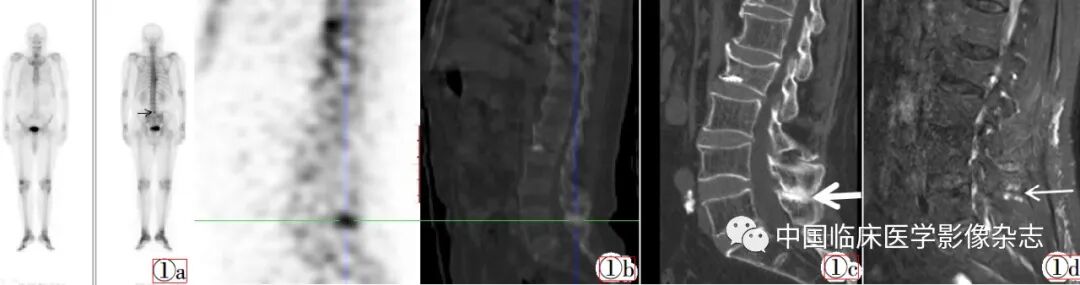

病例  例1:男,73岁,确诊前列腺癌1周,未治疗,腰疼半年,无外伤史,为了解有无骨转移行全身骨显像检查。检查方法:患者经静脉注射99mTc-MDP 925 MBq(25 mCi)(药物由由北京原子高科股份有限公司提供),3 h后采用通用电气公司生产的型号为Infinia vc hawkeye 4的SPECT/CT行全身骨前、后位静态显像并加做SPECT断层显像,静态显像采集能峰为140 keV,窗宽20%,矩阵256×1 024,探头旋转轨迹为自动人体轨迹。同机CT扫描参数,管电压140 kV,管电流2.5 mA,层厚4.42 mm,螺距l.9,矩阵512×512。采用机器自带后处理软件融合SPECT/CT图像,并进行矢状位、冠状位、横轴位重建。全身骨显像(图1)显示L5棘突放射性分布增高,断层CT定位于L4~L5椎体棘突间,可见相邻两棘突骨质增生硬化。腰椎CT显示L4~L5椎体棘突棘突间距离缩短,棘突相对缘骨质增生,密度增高、肥厚。腰椎MRI T2WI序列显示棘突间条带状高信号。临床诊断为Baastrup病。半年后随访患者腰痛持续存在,复查MRI,病变无显著变化。

图1  男,73岁,确诊前列腺癌1周。图1a:全身骨显像示L5棘突放射性分布增高(黑色箭头)。图1b:断层CT定位于L4~L5椎体棘突间,可见相邻两棘突骨质增生硬化(十字标识)。图1c:腰椎CT显示L4~L5椎体棘突间距离缩短,棘突相对缘骨质增生,密度增高、肥厚(白色粗箭头)。图1d:腰椎MRI T2WI序列显示棘突间条带状高信号(白色细箭头,全身骨显像所示T9椎体右侧放射性分布增高灶证实为骨质增生)。